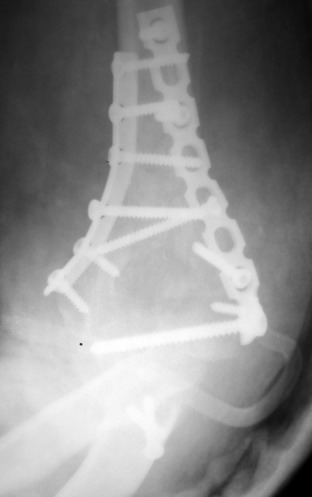

Солидарен с мнением обоих Александров (Челнокова и Рыкова): точную репозицию такого перелома вряд ли удастся выполнить закрыто. Даже во время открытого вмешательства это сделать непросто. Неслучайно предложен костно-пластический доступ с временным отсечением локтевого отростка. И по методу фиксации согласен с Александром Челноковым: 2 пластины. В качестве примера привожу рентгенограммы одного из наших пациентов с аналогичным повреждением.

С уважением, А. Золотов, Приморский край.